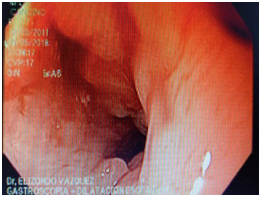

Figure 1 Esophagogram. July 7-17. No evidence of esophageal stricture 10days after liquid caustic ingestion.